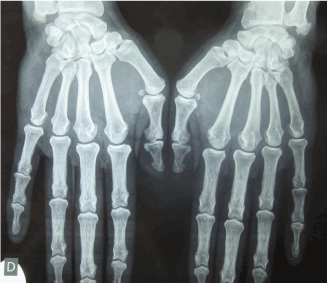

A 58-year-old man, who did not smoke, had worked for 21 years as a truck driver with exposure to silica, until the age of 52, when he developed dyspnea with polyarthritis involving wrists and ankles. He was referred to the Pneumology department in Farhat Hached Hospital in Sousse in Tunisia. He had dyspnea in effort stage II basing on NYHA classification. The pulmonary auscultation revealed crepitus in the basal segments. The exploration of respiratory function (EFR) showed a mild restrictive ventilatory deficit without alveolocapillary diffusion abnormalities. Chest X-rays revealed multiple micro-nodules distributed throughout the lungs but predominantly in lower segments (Figure 1). The bronchoalveolar lavage showed a predominance of macrophagic cells with predominance of 30% of siderophages. The CT scan of the chest showed a pulmonary fibrosis with septal and intralobular crosslinks in the two lung bases predominantly on the left side and at the upper lingual lobe (Figure 2). The diagnosis of silicosis was made in 2011. Then in 2016 he was referred to the rheumatology department, for exploration of chronic symmetrical polyarthritis. On physical examination, he presented synovitis in the shoulders, wrists, hands (Figure 3) and in the right knee. The X-Ray showed bilateral erosions in both hands (Figure 4) and feet (Figure 5). Rheumatoid factor (RF) found by the Latex and Rose-Waaler reaction and anti-cyclic citrullinated peptide antibodies (ACCP) measured by ELISA were highly positive (500 UI and 170 UI/L respectively). The patient was diagnosed with RA basing on the American College of Rheumatology (ACR)/European League against Rheumatism (EULAR) classification criteria of RA [6]. The disease activity score (DAS28) [7] was up for 7.52. The diagnosis of Caplan’s Syndrome was made. The patient received corticosteroids and rituximab (Mabthera®) with an improvement in polyarthritis with a 12 months follow-up.

Figure 4: Radiography of hands showing erosions in the left radial extremity, in the right carpe, in the first left inter-phalangeal joint and in the second and third right metacarpophalangeal joint.